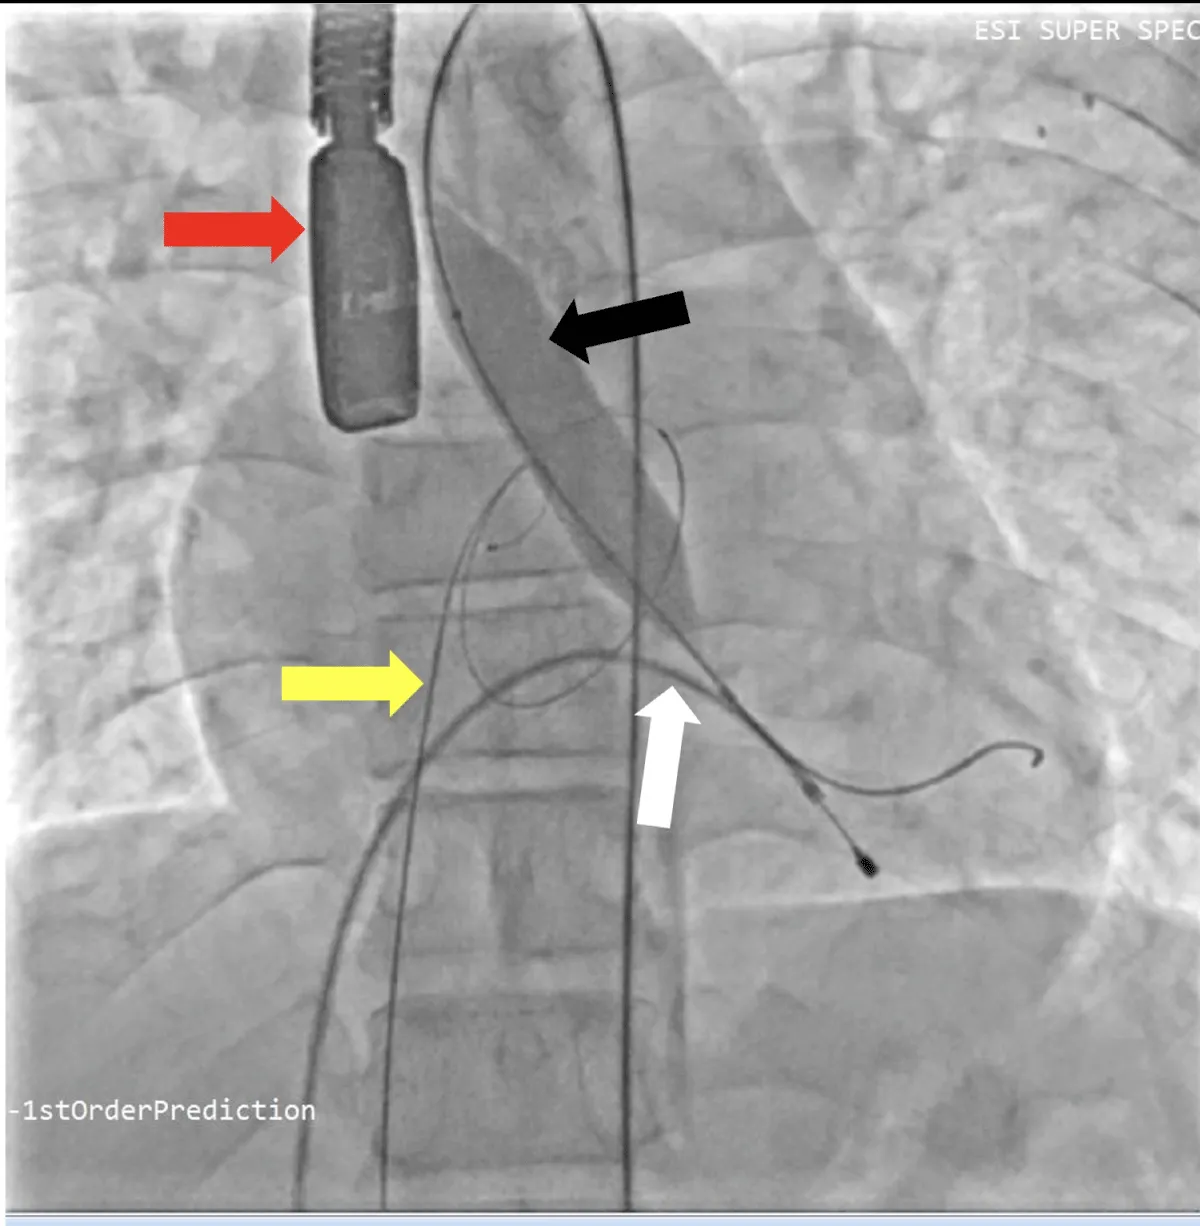

After obtaining consent, access was obtained through the right femoral vein and artery. Under 4D Transesophageal Echocardiography (4D TEE) guidance, the first transseptal puncture was performed with a broken Brough needle, and the LA wire was inserted through femoral venous access (Figure 1). Right femoral artery access was used for retrograde crossing of the aortic valve (AV) (Figure 2), and a Teflon wire was placed in the left ventricle. The aortic valve (AV) was dilated with a 14 mm ATLAS GOLD (BARD) balloon (Figure 3, Video 1).

Figure 3: Fluoroscopic image of aortic valve. Balloon dilatation of aortic valve under fluoroscopy and transoesophageal echocardiography (Red arrow), yellow arrow – Left atrial wire, white arrow- Right ventricular pacing lead, black arrow- Balloon across the aortic valve.

Following a single dilatation, the AV gradient decreased from 82 mm Hg to 30 mm Hg without aortic regurgitation (AR). Subsequently, the mitral valve (MV) was dilated with a 26 mm Inoue balloon (Figures 4,5) (Video 2). After a single dilatation, the MV gradient was reduced from 35/21 mm Hg to 12/5 mm Hg, and the MV area increased from 0.5 cm2 to 1.6 cm2 (Figure 6)